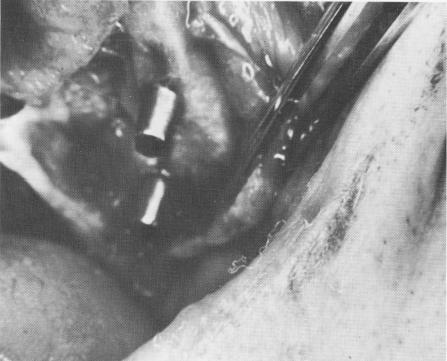

Fig. 7-42. Thick tissue may be removed with a scalpel while the implant is in place.

2 Thick tissues removed with scalpel, endosseous blade implant in place